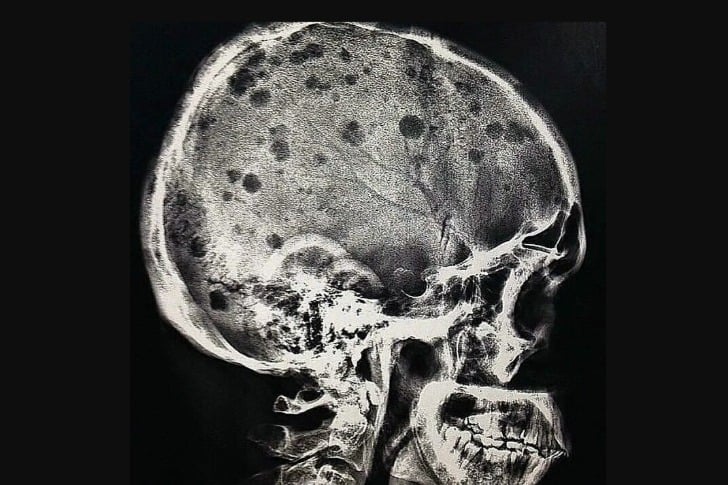

#32 Un paciente con mieloma múltiple

El aspecto radiográfico clásico del mieloma múltiple es el de múltiples lesiones pequeñas, bien circunscritas, líticas, “perforadas” y redondas dentro del cráneo, la columna vertebral y la pelvis. El patrón de lesiones radiolúcidas líticas o “perforadas” en el cráneo se ha descrito como parecido a gotas de lluvia golpeando una superficie y salpicando.